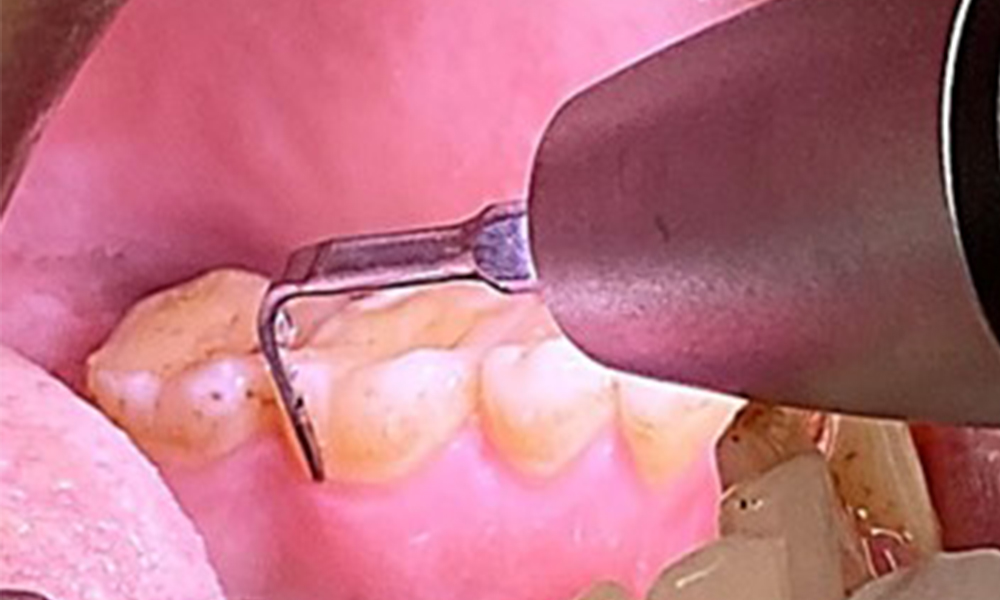

In der Instrumentierung der Therapiesitzung ergeben sich bezüglich der Methodenwahl aufgrund des gesunden Allgemeinzustandes des Patienten keine Einschränkungen. Gegebenenfalls ist in der Allergiephase individuell abzuklären, ob der Patient Einschränkungen beim Atmen hat. In diesem Fall ist abzuwägen, ob das Pulverstrahlgerät zum Einsatz kommen sollte.

Ziel ist es durch supra- und subgingivale Biofilmentfernung das Erkrankungsrisiko zu kontrollieren. Die Wahl der Instrumente erfolgt

bedarfsgerecht. Zunächst sind Zahnstein und ggf. Konkremente mit Ultraschall und / oder Handinstrumenten zu entfernen (Abb. 10).

Anwendung eines piezobetriebenen Ultraschallgerätes in Rg 36

Abb. 10 Anwendung eines piezobetriebenen Ultraschallgerätes in Rg 36 lingual (hier Proxeo Ultra, Firma W&H), © Dr. R. Krapf